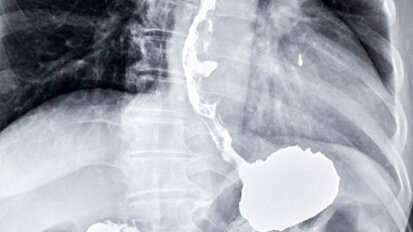

Un test sul respiro per diagnosticare il cancro dell’esofago e dello stomaco

Londra, Regno Unito. Un team internazionale di ricercatori ha sviluppato un test del respiro che potrebbe aiutare i medici a diagnosticare i segni precoci ...